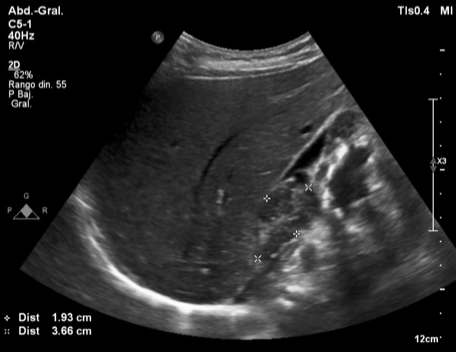

Hallazgos ecográficos

Hígado de tamaño, morfología y ecoestructura conservadas, con un quiste simple y sin alteraciones significativas en la vesícula, la vía biliar y el área pancreática. Tanto el bazo como los riñones sin hallazgos significativos. Sin embargo, se observan múltiples adenopatías en hilio hepático. Hallazgo inesperado que motiva la ampliación del estudio con gastroscopia y ecografía abdominal reglada preferentes.